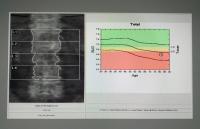

Bone loss is, of course, invisible. To detect decreased bone mass in the skeleton before the first fracture occurs, clinicians rely on the non-invasive scanning technology known as DXA (short for dual-energy X-ray absorptiometry and pronounced “dexa”).

Bone density scan results. To detect decreased bone mass in the skeleton, clinicians rely on a non-invasive scanning technology known as DXA (short for dual-energy X-ray absorptiometry and pronounced “dexa”). Photo from Getty Images.

Like a regular X-ray, a DXA scan uses low-dose radiation, is fast and painless, and doesn’t involve any injections. Plan on 15 to 20 minutes for the procedure.

DXA measures how much of the X-ray passes through the bone and converts this to a density measurement. The lower the mineral content, the more the X-rays pass through the bone.